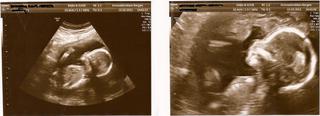

takpovediac, som si to dnes chcela overiť, že ako sa nám darí, takže @gabikri a ostatné dievčence, nech sa páči foto:

Ja som bola predvcerom na UTZ a dozvedeli sme sa ze nas chlapcek, bude vlastne dievcatko 🙂 Ma 17-18cm a je krasna.Tak sa teraz snazime preorientovat na ruzovu. 🙂 Ale velmi milo nas to prekvapilo a stary rodicia su tiez nadseny. U manzela v rodine su sami chlapi a vsetci tuzia po dievcatku 😀 Prikladam fotku nasej princeznicky